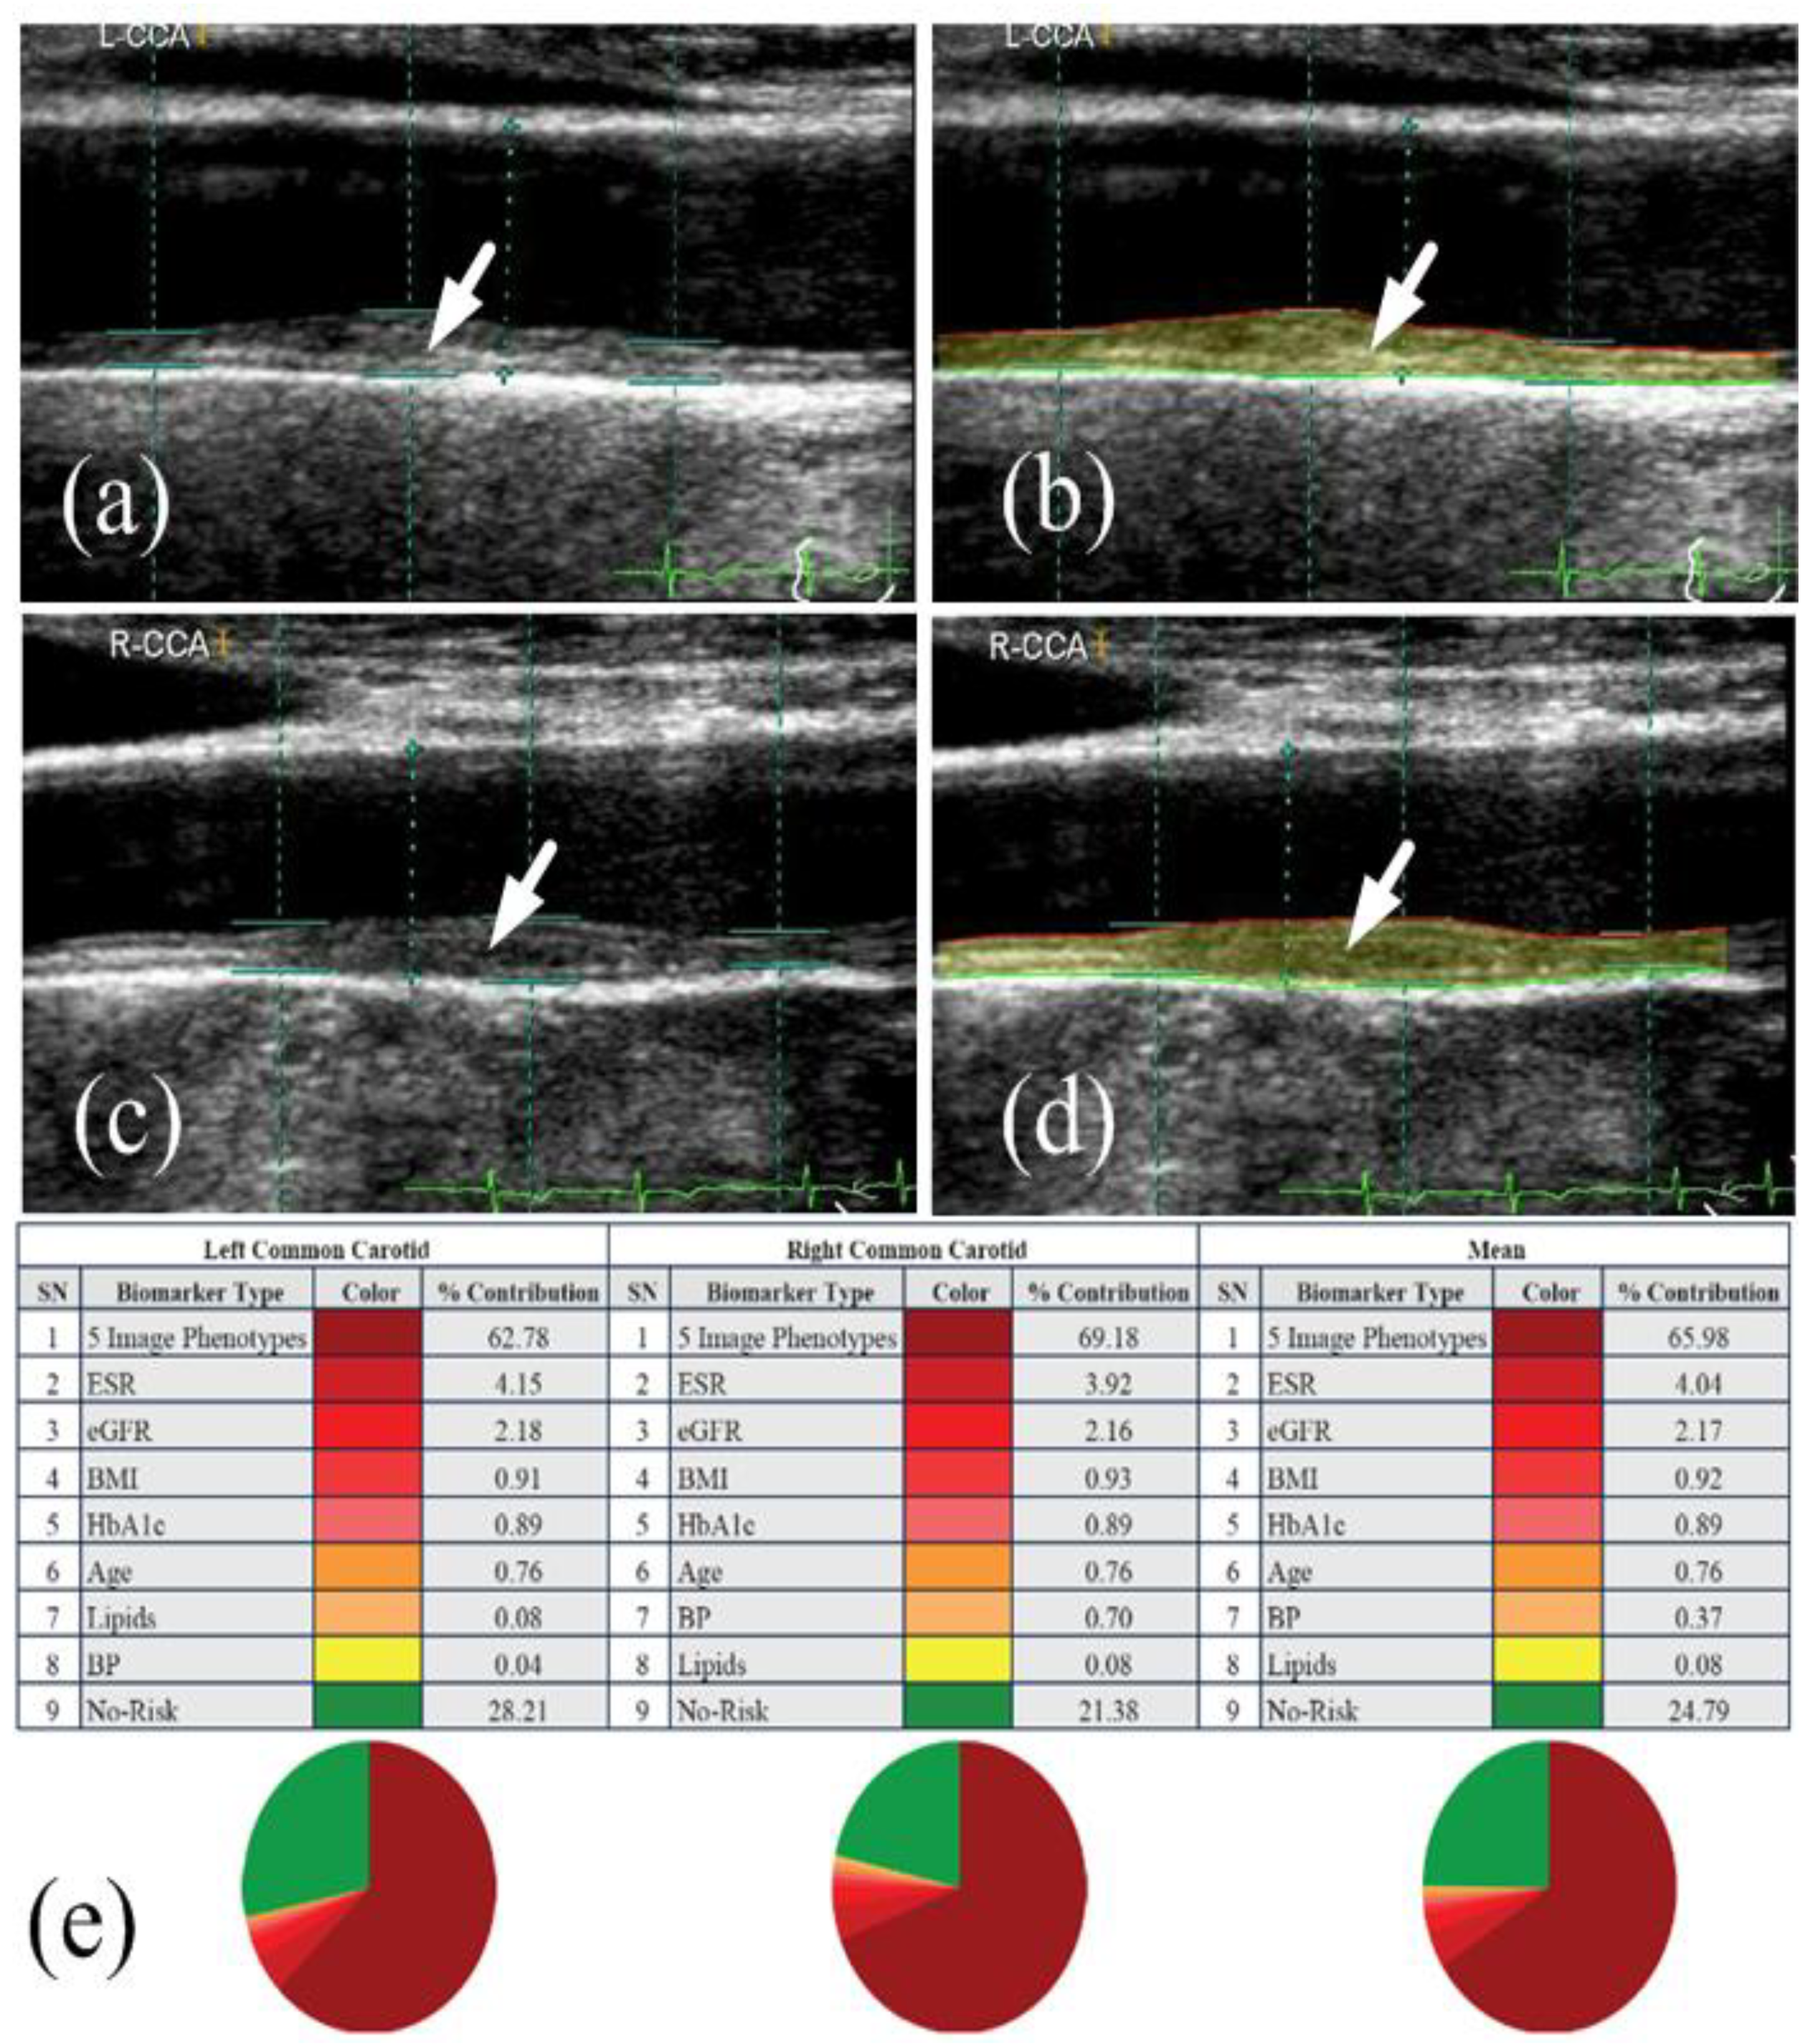

- Kotsis, V.; Jamthikar, A.; Araki, T.; Gupta, D.; Laird, J.R.; Giannopoulos, A.A.; Saba, L.; Suri, H.S.; Mavrogeni, S.; Kitas, G.D.; et al. Echolucency-based phenotype in carotid atherosclerosis disease for risk stratification of diabetes patients. Diabetes Res. Clin. Pract. 2018, 143, 322–331. [Google Scholar] [CrossRef]

- Khanna, N.N.; Jamthikar, A.; Araki, T.; Gupta, D.; Piga, M.; Saba, L.; Carcassi, C.; Nicolaides, A.; Laird, J.R.; Suri, H.S.; et al. Nonlinear model for the carotid artery disease 10-year risk prediction by fusing conventional cardiovascular factors to carotid ultrasound image phenotypes: A Japanese diabetes cohort study. Echocardiography 2019, 36, 345–361. [Google Scholar] [CrossRef]

- Khanna, N.N.; Jamthikar, A.D.; Gupta, D.; Araki, T.; Piga, M.; Saba, L.; Carcassi, C.; Nicolaides, A.; Laird, J.R.; Suri, H.S.; et al. Effect of carotid image-based phenotypes on cardiovascular risk calculator: AECRS1.0. Med. Biol. Eng. Comput. 2019, 57, 1553–1566. [Google Scholar] [CrossRef]

- Jamthikar, A.; Gupta, D.; Khanna, N.N.; Saba, L.; Araki, T.; Viskovic, K.; Suri, H.S.; Gupta, A.; Mavrogeni, S.; Turk, M.; et al. A low-cost machine learning-based cardiovascular/stroke risk assessment system: Integration of conventional factors with image phenotypes. Cardiovasc. Diagn. Ther. 2019, 9, 420–430. [Google Scholar] [CrossRef] [PubMed]